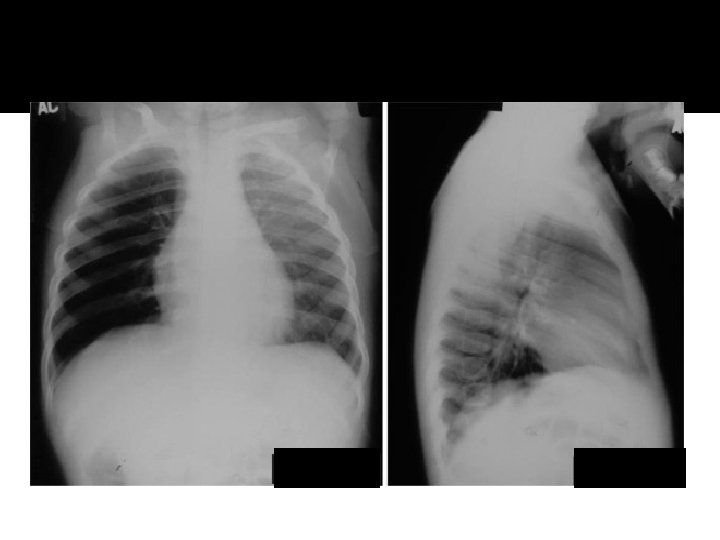

Atelectasis RML

Pneumonia lingula

Atelecasis RML